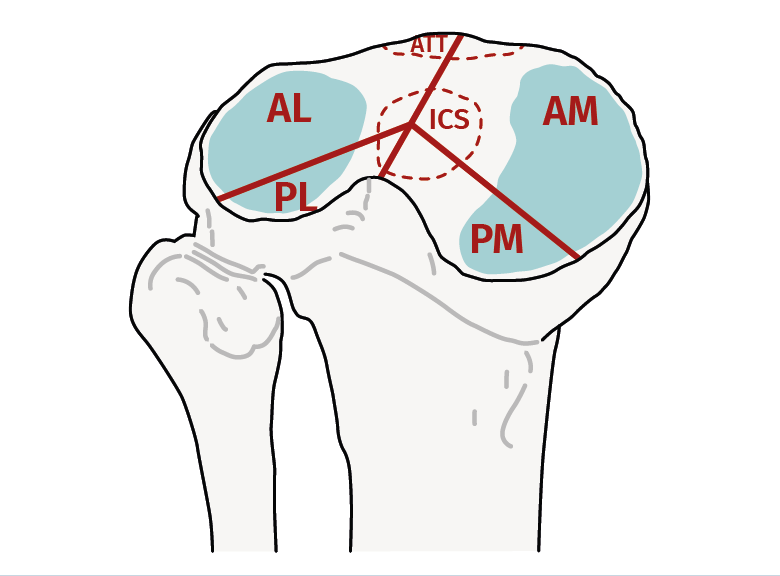

Posteriormente, en 2014, Chang et al.(11) dividen las fracturas de platillos tibiales en 4 columnas: anteromedial, anterolateral, posteromedial y posterolateral, con el fin de mejorar la caracterización de los fragmentos posteriores y así su tratamiento (Figura 3)(12). Además, se ha demostrado que esta clasificación posee los más altos porcentajes de concordancia intra- e interobservador, con diferencias estadísticamente significativas respecto a las clasificaciones clásicas(13).

Figura 3. Concepto de las 4 columnas, similar a las 3 columnas, pero divide la columna posterior en 2 (posterolateral y posteromedial)(12).